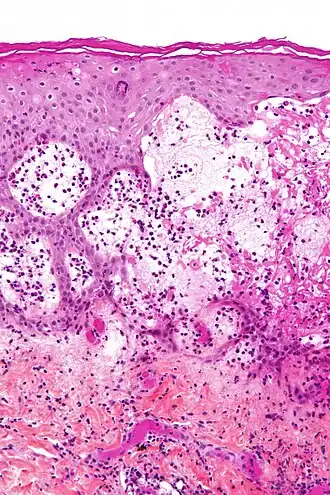

Herpes gestationis is een huidziekte met blaren en ernstige jeuk, die zeer zelden in de zwangerschap optreedt. Omdat de aandoening weinig met herpes (een virusinfectie) te maken heeft, maar meer met pemfigoïd (een auto-immuunziekte) is pemphigoides gestationis een duidelijker naam.

Rond de navel ontstaan huidafwijkingen die leiden tot blaren, de ziekte breidt zich dan hiervandaan uit. Net als bij veel andere auto-immuunziekten is de oorzaak niet goed begrepen. Net als bij bulleus pemfigoïd worden antistoffen gevormd tegen eiwitten van de hemi-desmosoom die de opperhuid aan de lederhuid verankert, meestal tegen collageen XVII, soms tegen BP230. Deze antistoffen verzwakken de aanhechting, en daardoor ontstaat blaarvorming.